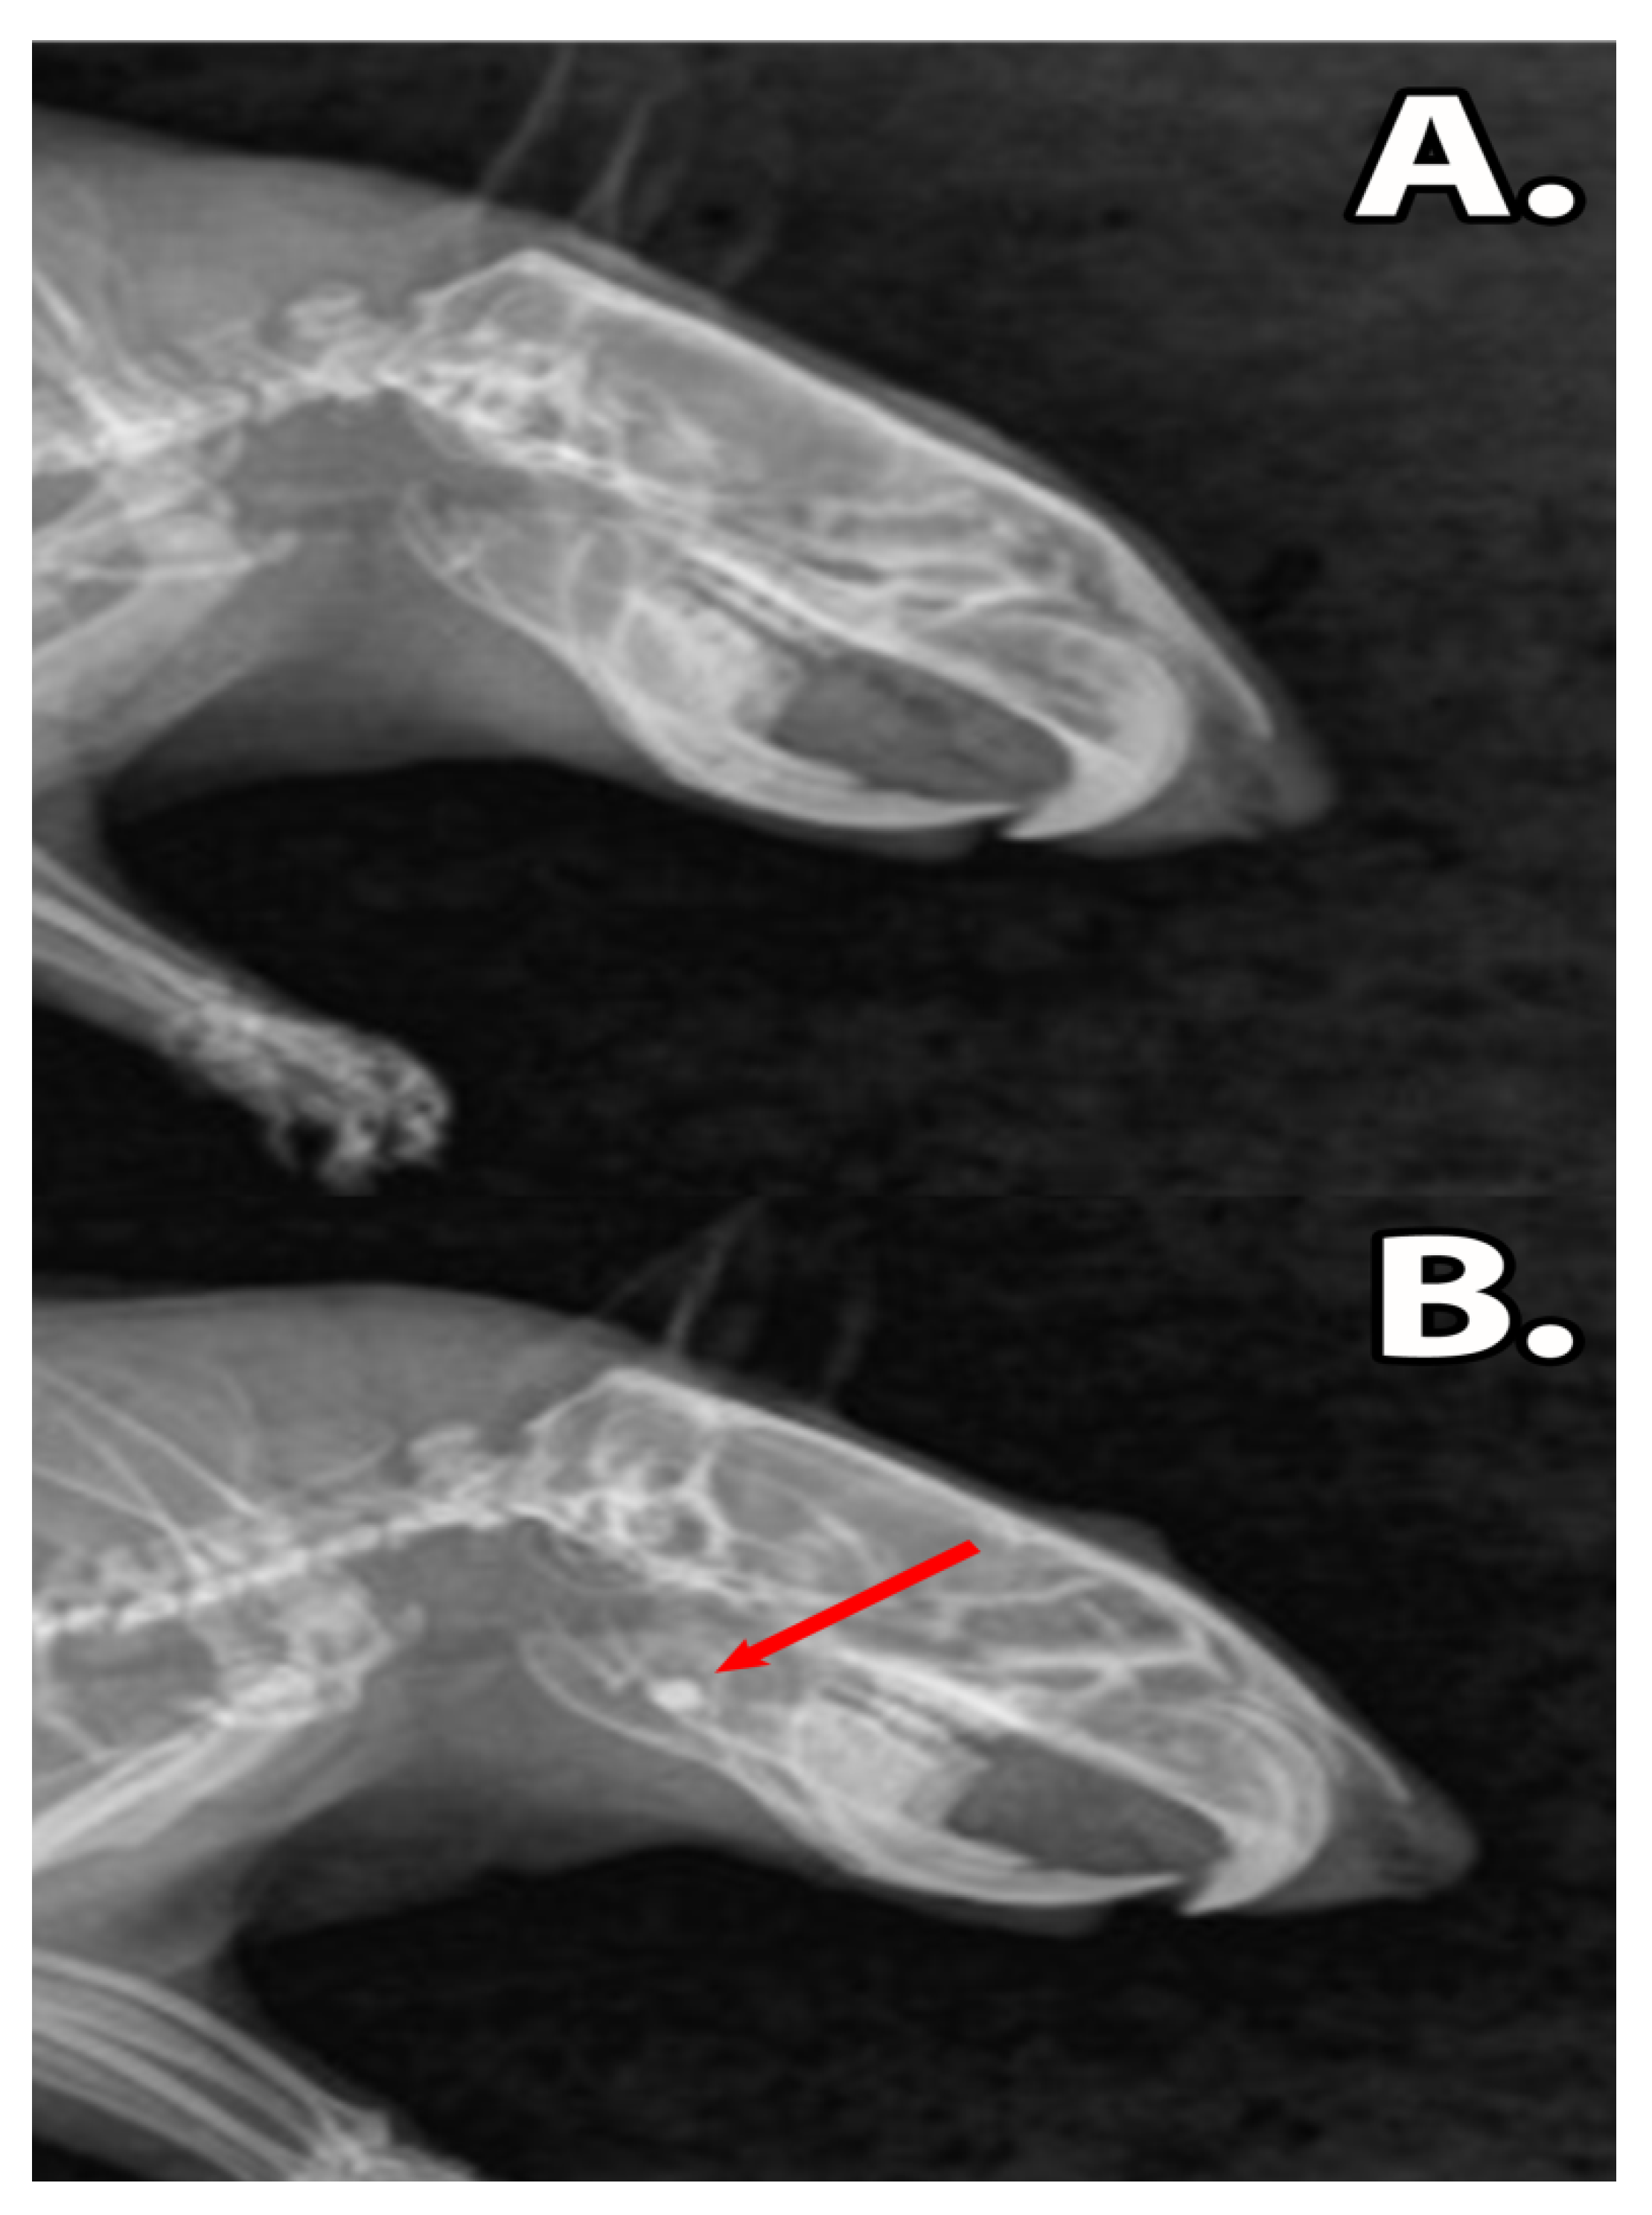

3.2. Clinical Assessment

3.5. Histology of the Bone Defect